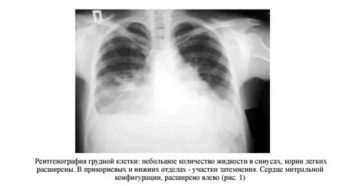

Расшифровка снимка легких: таблица кодов Основная диагностическая методика, позволяющая выявить лёгочную патологию — рентгенография. Правильная…